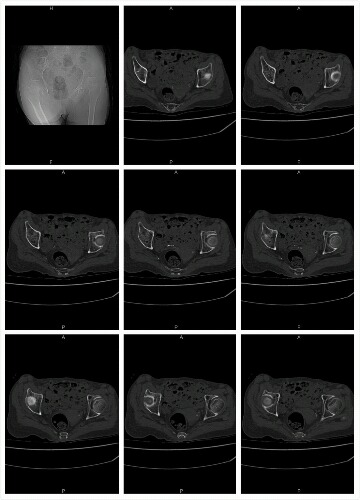

CT51172:股骨

女,87 二十天前摔伤

右侧股骨颈骨折

右股骨头颈短缩,股骨头密度高低不均,关节囊积液,周围软组织肿胀,考虑 右股骨头颈坎顿性骨折伴关节囊积液,建议结合临床,MRI检查。

右股骨头颈变短并成角畸形,骨质内见高低密度影,周围软组织肿胀内见更低密度影,会不会是骨TB并骨折